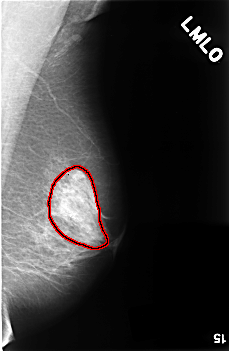

C_0458_1.LEFT_MLO

FILE: C_0458_1.LEFT_MLO.OVERLAY

TOTAL_ABNORMALITIES 1

ABNORMALITY 1

LESION_TYPE CALCIFICATION TYPE PLEOMORPHIC DISTRIBUTION SEGMENTAL

ASSESSMENT 5

SUBTLETY 5

PATHOLOGY MALIGNANT

TOTAL_OUTLINES 1

BOUNDARY